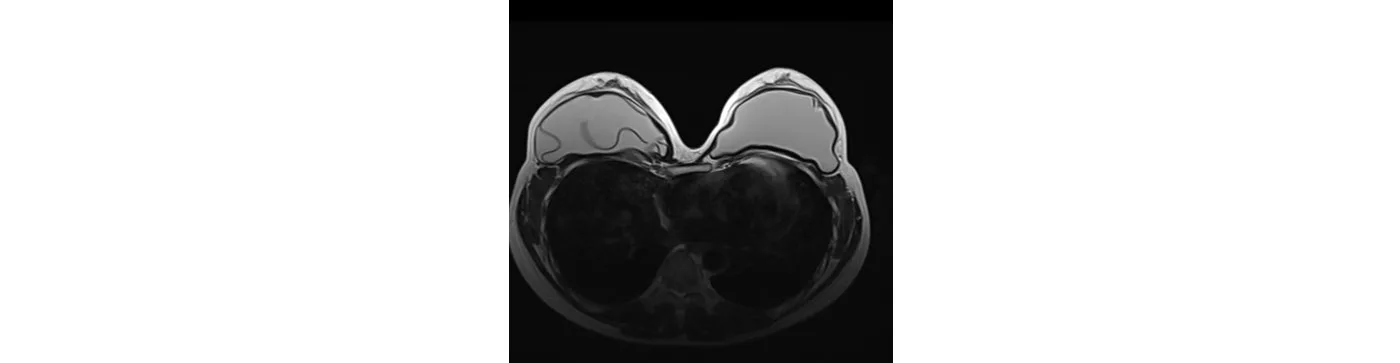

A 36-year-old female has a check-up after 5 years of breast augmentation. The MRI diagnosed implant rupture in the right chest.